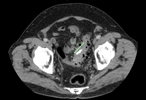

Endovascular intervention for iliac vein thrombosis after simultaneous kidney-pancreas transplant

Meredith Gunder and others

Journal of Surgical Case Reports, Volume 2019, Issue 4, April 2019, rjz024, https://doi.org/10.1093/jscr/rjz024